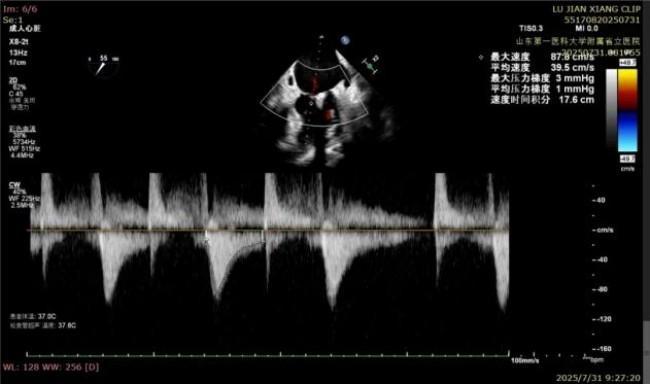

手术过程中,麻醉与围术期医学科副主任医师马金本确保麻醉过程平稳。心脏大血管外科主治医师董明亮穿刺股静脉置入血管鞘,并在心脏超声科梁皓主任及段福建教授TEE引导下,顺利穿刺房间隔,房间隔穿刺高度4.9cm。随后,在王安彪主任以及刘洋教授指导、心脏超声科梁皓主任TEE引导下,董明亮医师沿输送系统将延展呈“一字型”状态的国产夹合器送至左房,缓慢关闭夹合器并进行弹道测试。调整夹合器位置和方向后,董明亮医师再次将夹合器延展呈“一字型”完成跨瓣,避免发生腱索缠绕,成功捕获瓣叶后关闭夹合器,二尖瓣反流显著下降。夹合器完全解离后,超声示二尖瓣反流程度显著下降,残余反流0,平均跨瓣压差1mmHg,手术圆满成功。

平均跨瓣压差